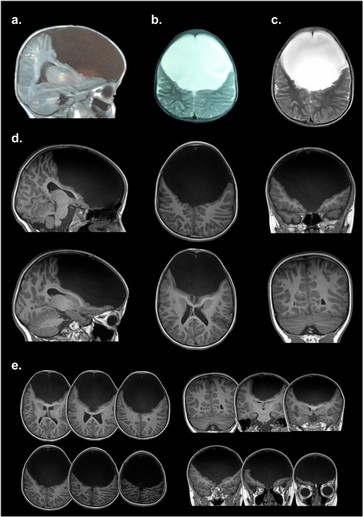

Gabriela Garcia Gutiérrez es una niña nacida en Cali con una particularidad única que desvela a la ciencia: nació sin los lóbulos frontales del cerebro.

Gabriela García Gutiérrez es una niña nacida en Cali, Colombia, muy alegre e inteligente, que vive con su familia y concurría hasta hace 3 años a la escuela. Pero con un particularidad única que desvela a la ciencia: nació sin los lóbulos frontales del cerebro, los cuales según los expertos, ocupan un tercio de la corteza cerebral y son los encargados de regular las emociones y sentimientos.

"Gabriela carece del lóbulo frontal, que es la parte más evolucionada que tiene el cerebro. Allí se determina el control de la conducta, el procesamiento de las emociones, los deseos, las llamadas ejecutivas de determinada acción, el lenguaje y otras más. Esa porción cerebral es realmente como una computadora compleja, donde se mantienen más conexiones. La niña presenta solamente un 10% de esa corteza prefrontal, pero al estudiarla vimos que no tiene ninguna conexión cerebral", sostuvo Ibañez.

Katherine decidió contactarse con los médicos argentinos que actualmente tratan a su hija ya que consideró que en Colombia la habían diagnosticado y tratado muy mal. Inclusive, los médicos colombianos pensaron que se trataba de un caso de hidrocefalia y la operaron para colocarle una válvula que drenara el líquido. Gabriela pasó varios días en terapia intensiva recuperándose de una operación que no sirvió de nada. Pero su fuerza de voluntad la ayudó a sobrellevar ese trauma.

Antes de viajar a conocerla, el doctor Ibañez vio las resonancias efectuadas en su cerebro y pensó que no caminaba, por carecer de corteza motora, o que no hablaba, porque le faltaba las áreas de Broca.

"Si bien las imágenes estructurales muestran la ausencia del lóbulo cerebral, la tractografía y conexiones de neuronas se reorganizaron de forma plástica desde su concepción en el seno materno y durante su niñez. También observamos que las conexiones funcionales, las redes por donde se transmiten las órdenes cerebrales se reorganizaron", aclaró el profesional.